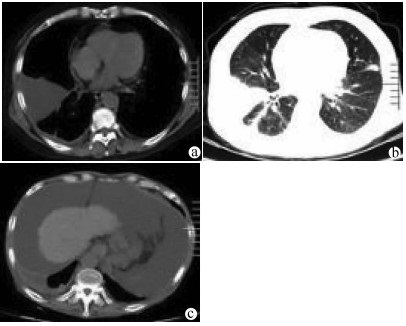

高原地区体外肝切除联合自体肝移植术治疗晚期肝泡型包虫病的术后并发症及其防治策略

田青山, 冯少培, 郭亚民, 韩秀敏, 赵顺云, 叶成杰, 安永德, 吴世乐, 王向前, 郑海波, 朱文君, 阿吉德, 高伟, 潘洪帅

2021, 37(9): 2153-2160. DOI: 10.3969/j.issn.1001-5256.2021.09.029

摘要(1294) HTML (489) PDF (3321KB)(55)

摘要:

目的  探讨高原地区体外肝切除联合自体肝移植术治疗终末期肝泡型包虫病的术后并发症并探讨防治策略。  方法  收集青海省人民医院2013年1月— 2019年3月接受自体肝移植术的11例终末期肝泡型包虫病患者的手术资料及随访资料,对术中及术后情况进行分析。  结果  11例患者均成功行自体肝移植术,无术中死亡,其中2例(18.18%)行半离体肝切除,9例(81.82%)行全离体肝切除。肝后下腔静脉重建方式中,采用自体大隐静脉进行重建者2例(18.18%),采用人造血管重建者4例(36.36%),5例(45.45%)保留自体肝后下腔静脉。胆道重建方式中,8例(72.73%)行胆肠吻合术,3例(27.27%)行胆管端端吻合术。11例患者的术后并发症主要有出血2例(18.18%);胆汁漏、腹腔感染4例(36.36%),胆肠吻合口狭窄1例(9.09%), 血栓2例(18.18%),肺部感染、胸腔积液2例(18.18%);包虫复发1例(9.09%)。11例患者发生围术期死亡2例(18.18%),其余9例(81.82%)患者均好转出院。  结论  出血、胆道并发症和感染是造成高原地区自体肝移植患者死亡的主要原因,精准把握手术适应证、术前仔细多学科评估、术中精湛的操作、外科技术流程的标准化及精细的围术期管理是降低自体肝移植术围术期病死率、避免和减少术后并发症以及使患者获得长期良好生存的关键。